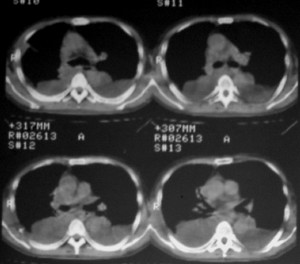

m ,60岁,右上肺ca术后一月。

右侧肺癌术后:肝内可见多个大小不等的低密度结节影。腹腔及双侧胸腔大量积液。考虑:肺癌并胸膜及肝脏转移。

纵隔淋巴结增大,双侧胸水。考虑术后残留,而非复发。

肺癌术后 。双侧胸水 纵隔 胸膜 肝脏转移